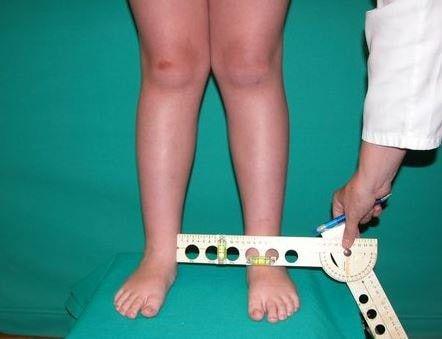

دسامبر 23, 2019عقب زدگی زانو یا Genu Recurvatum یک تغییر شکل در مفصل زانو است ، به نحوی که زانو به سمت عقب تمایل می یابد.

به عبارتی دیگر ژنورکورواتوم یک اکستانسیون(صاف شدن) بیش از اندازه در مفصل زانو است.

دامنه حرکتی طبیعی مفصل زانو در یک فرد بزرگسال ،صفر الی ۱۳۵ درجهاست. دامنه صفر درجه مربوط به صاف بودن کامل (اکستانسیون کامل) زانو در یک فرد طبیعی است. خم شدن زانو به عقب باعث افزایش زاویه اکستانسیون میگردد.

- اندازه گیری میزان اکستانسیون زانو